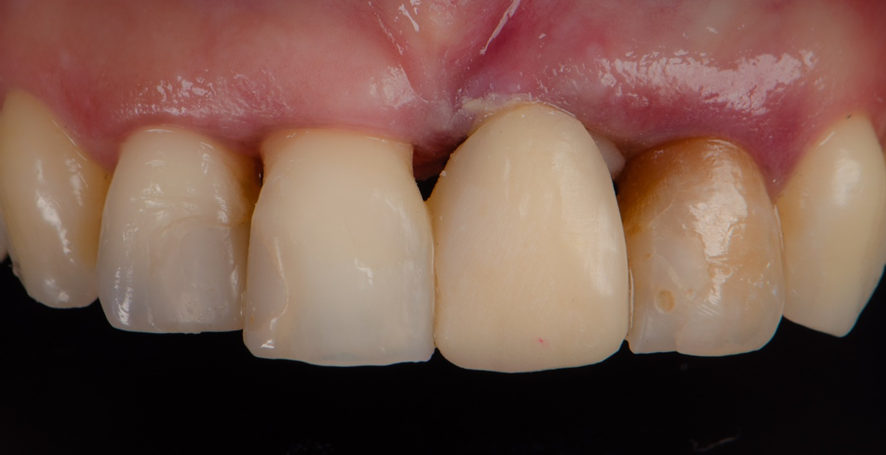

Pilar provisório posicionado.

Uma provisória ferulizada foi então instalada, presa aos dentes adjacentes.